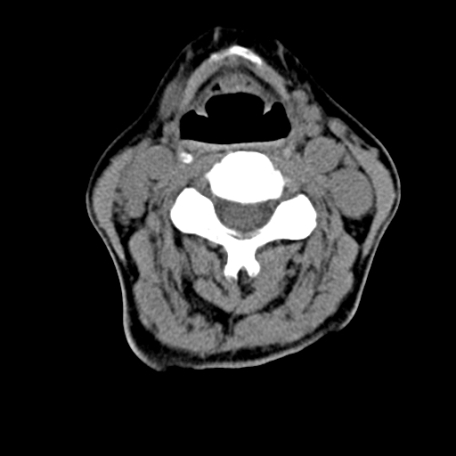

标题: CT24010:患者女56岁双侧甲状腺摘除术后一月复查,患者现感 [打印本页]

标题: CT24010:患者女56岁双侧甲状腺摘除术后一月复查,患者现感

甲状腺术后复发,现在甲状腺区域仍有密度不均匀之软组织密度影。

甲状腺区域密度不均匀密度影,应该是术后改变,要鉴别是否复发,建议增强检查。

“甲状腺摘除术后一月复查”,有病理吗?考虑术后复发,可能是恶性,颌下及左侧颈部淋巴结有肿大。

考虑术后复发,并颈部淋巴结肿大。请结合临床。

双侧甲状腺肿大,伴多发低密度灶(性质待定);建议行进一步检查。

双侧甲状腺肿大,周围结构不清,术后复发时间有点短,考虑出血并感染。